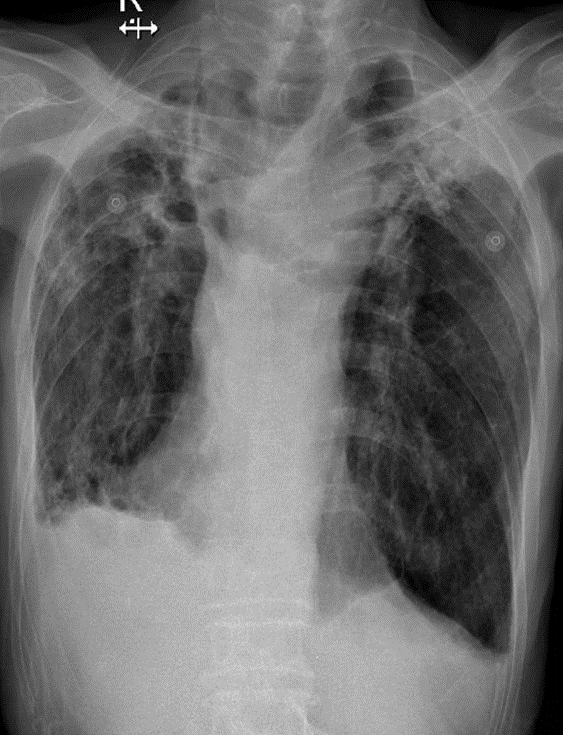

Hãy phân tích tình huống nữ 86 tuổi

1-Khí quản lệch(P) 2-Xơ xẹp đỉnh phổi hai bên 3-Tràn dịch + dày dính màng phổi hai bên